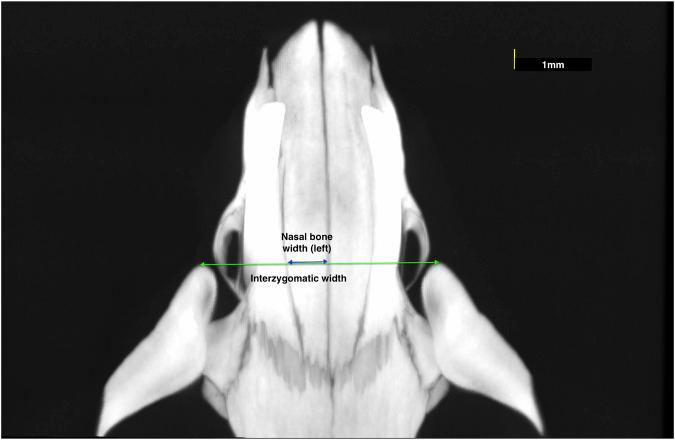

To evaluate the dimensional changes that occur in the internasal and nasopremaxillary sutures, and related transverse craniofacial dimensions, of rats from 4 to 38-weeks of age. Four groups of twelve male Wistar rats were sacrificed at different ages [4-weeks (immature), 16-weeks (adolescent), 26-weeks (young adult), 38-weeks (adult)]. The rats were scanned with a high-resolution micro-computed tomography imaging device with 90 µm voxel size and 45 mm × 45 mm field of view (FOV) to obtain images of the viscreocranium, and with 10 µm voxel size and 5 mm × 5 mm FOV to obtain images of the internasal and left nasopremaxillary sutures. The nasal bone width, transverse width between the nasopremaxillary sutures and interzygomatic width were measured as craniofacial measurements. The endocranial, ectocranial and mean suture widths (cross-sectional area between endocranial and ectocranial borders/suture height), and suture height were measured at 5 frontal planes with 1.2 mm intervals. Outcomes were compared at different ages, and correlation coefficients were used to assess the relationship between craniofacial and suture changes. All transverse craniofacial dimensions increased significantly from 4-16 weeks of age ( < 0.001). After 16-weeks of age, the only significant increase was observed in interzygomatic width ( = 0.02), between 26 and 38 weeks. In both the internasal and nasopremaxillary sutures, the endocranial suture mean widths decreased from 4-16 weeks ( < 0.001 and = 0.002, respectively), but did not show any significant change after 16-weeks of age. The ectocranial internasal suture width decreased from 4-16 weeks ( < 0.001), increased until 26-weeks ( = 0.035), and subsequently decreased ( < 0.001). The nasopremaxillary suture widths decreased from 4-38 weeks to varying degrees in different frontal planes. Except for the internasal ectocranial suture width, all suture measurements were found highly and negatively correlated with the transverse craniofacial dimensions. The height of the sutures increased with time, with the most significant changes occurring between 4 and 16 weeks of age ( < 0.001). Although the internasal and nasopremaxillary endocranial suture widths nearly reach their final widths during adolescence, the changes in the ectocranial and mean suture widths continue into early adulthood. These results may serve as a reference for future studies aiming to evaluate the effects of functional demands on suture development and dimensional changes of the viscerocranium.

评估4至38周龄大鼠鼻内缝和鼻前上颌缝以及相关横向颅面尺寸的变化。将四组每组12只雄性Wistar大鼠在不同年龄(4周龄,未成年;16周龄,青春期;26周龄,青年成年期;38周龄,成年期)处死后,用体素大小为90微米、视野为45毫米×45毫米的高分辨率微型计算机断层扫描成像设备对大鼠进行扫描,以获取面颅骨的图像,并用体素大小为10微米、视野为5毫米×5毫米的设备获取鼻内缝和左鼻前上颌缝的图像。测量鼻骨宽度、鼻前上颌缝之间的横向宽度和颧骨间宽度作为颅面测量指标。在内颅、外颅和平均缝宽(内颅和外颅边界之间的横截面积/缝高)以及缝高方面,在5个间隔为1.2毫米的额平面上进行测量。比较不同年龄的结果,并使用相关系数评估颅面和缝变化之间的关系。所有横向颅面尺寸在4至16周龄时显著增加(<0.001)。16周龄后,仅在26至38周龄之间观察到颧骨间宽度有显著增加(=0.02)。在鼻内缝和鼻前上颌缝中,内颅缝平均宽度在4至16周龄时减小(分别为<0.001和=0.002),但在16周龄后未显示出任何显著变化。外颅鼻内缝宽度在4至16周龄时减小(<0.001),在26周龄前增加(=0.035),随后减小(<0.001)。鼻前上颌缝宽度在不同额平面上从4至38周龄有不同程度的减小。除了鼻外颅缝宽度外,所有缝测量值与横向颅面尺寸高度负相关。缝高随时间增加,最显著的变化发生在4至16周龄之间(<0.001)。虽然鼻内缝和鼻前上颌内颅缝宽度在青春期几乎达到最终宽度,但外颅和平均缝宽的变化持续到成年早期。这些结果可为未来旨在评估功能需求对缝发育和面颅骨尺寸变化影响的研究提供参考。